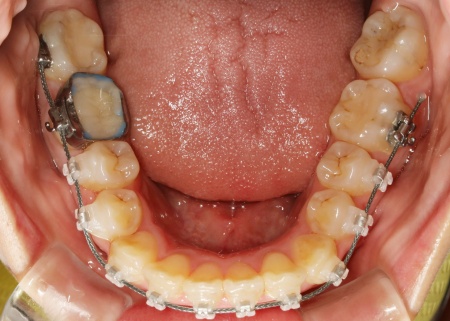

20代女性 ワイヤー矯正とマウスピース矯正を併用したハイブリッド矯正で歯並びを改善した症例

また上下とも歯の移動量が多いため、ワイヤー矯正である程度移動を行ったのち、マウスピース矯正で仕上げを行う「ハイブリッド矯正」を提案しました。

続いて、上下の歯の表面に金属のブラケットよりも目立ちにくい「セラミックブラケット」を接着し、ワイヤー矯正を開始しました。

ワイヤー矯正である程度歯並びが整ったら、マウスピース矯正に移行します。